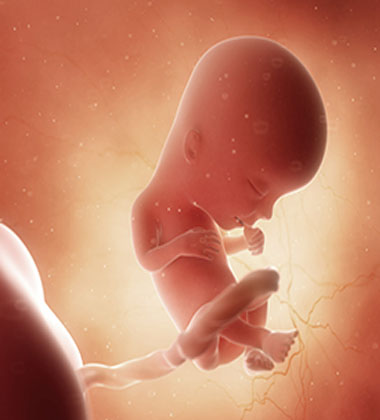

13 haftalık gebelik görüntüsü ile bebek önceki haftalara göre çok daha net görülebilir. 4D ultrason cihazları kullanılarak yapılan taramalarda bebeğin gülümsemesi veya çeşitli yüz ifadeleri bile görülebilir. Hızlı deri ve kemik gelişimi ile bebek bu hafta itibariyle insan formuna daha da yaklaşır. Beyin gelişiminin diğer organlardan daha erken olduğu için bebeğinizin başı vücuduna kıyasla büyük görünecektir. İstemli hareketler henüz olmasa da ultrasonda bebeğin bazı hareketleri belirlenebilir. Genellikle 13.haftada gerçekleştirilen bir ultrason muayenesi ile doktorunuz bebeğin gelişimi, ekstremitelerinin durumu gibi bir dizi konuda bilgi sahibi olabilir. Bazı anne adayları 13. hafta için bebek görüntülerini arama eğilimindedir ancak bilimsel kaynaklardan ve kendi bebeğinizin ultrason görüntülerinden yararlanmanız daha sağlıklı olacaktır. Her türlü sorunuz için en doğru bilgiyi doktorunuzdan alabileceğinizi unutmayın.

Gebeliğin 13. haftası, anne gibi bebekte de bir dizi gelişme getirir. Ultrasonda görülebileceği gibi artık küçük bir insan olduğu açıkça anlaşılan bebek 6.5-8 cm uzunluğunda ve yaklaşık 13-20 gram ağırlığındadır. Bu haftadaki bir bebek genellikle bir limon büyüklüğündedir. Önceki ultrason incelemelerinde bebeğinizin başının ve gövdesinin boyutlarının neredeyse aynı olduğunu fark etmiş olabilirsiniz. Ancak beyin gelişiminin hızla ilerlemesi sebebiyle 13. haftada yapılan bir ultrasonda başın büyüklüğünün gövdenin birkaç katı kadar olduğunu görmek mümkün olabilir. Bu haftadan itibaren başın büyüme hızı yavaşlayacak ve beden daha hızlı büyümeye devam edecektir. Gebeliğin ilk haftalarında bebeğinizin bağırsakları primitif bir yapıda gelişiyordu ve göbek kordonunda bulunuyordu. Ancak bu haftadan itibaren bağırsaklar bebeğinizin karın boşluğundaki kalıcı konumlarına doğru yerleşmeye başlar. Başın yanında yer alan gözler birbirine yaklaşır, kulaklar ve yüz yapısı çok daha belirginleşir. Ses telleri gelişirken cinsel organ detaylı bir ultrason ile görünebilecek düzeye gelir. Karaciğer ve pankreas gibi bazı organlar ise bu hafta faaliyetlerine başlar. Bebek amniyon sıvısını yutmaya ve soluk alıp vermeye başlarken böbrekler idrar üretmeye başlamıştır ki bu idrar amniyon sıvısına dönüşebilir.

Önceki haftalara kıyasla bu hafta bebeğiniz daha hızlı büyüyecek ve gelişecektir. Organların yerleşmeye başladığını ve bazılarının çalışmaya başladığını belirtmek mümkün. Bu bilgi ışığında 13 haftalık bir bebek ne aşamadadır inceleyelim.

Hamileliğin 13. haftasında gerçekleştirilen ultrason muayenesinde, bebeğin görüntüsü daha netleşmeye başlar ve büyüklük olarak yaklaşık bir bezelye tanesine eşittir. Bebeğin başı, vücudu, kolları ve bacakları artık daha belirgin hale gelmiştir ve minyatür bir insan şekline bürünmüştür. Ultrasonda bebeğin kol ve bacak hareketlerinin yanı sıra diğer aktivitelerini de izlemek mümkündür. Ultrason ile bebeklerin kol, bacak ve el hareketleri açıkça izlenebilir. 13 haftalık bir gebelikte bebeği daha ayrıntılı bir şekilde görmeyi sağlayan 4 boyutlu ultrason görüntüleme seçeneği bulunmaktadır.